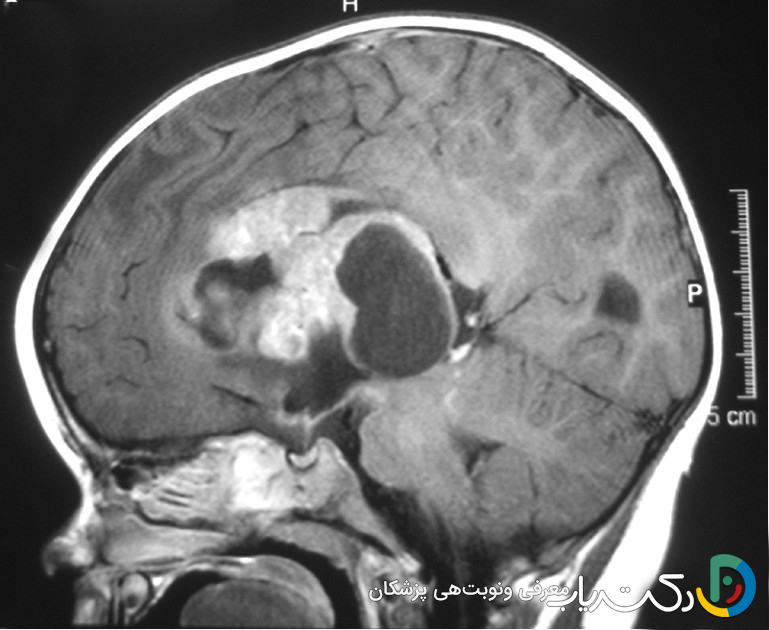

2. تصویربرداری مغز: این بخش مهم‌ترین مرحله تشخیصی است.

• MRI (تصویربرداری تشدید مغناطیسی): این روش به دلیل نمایش جزئیات دقیق بافت نرم مغز، استاندارد طلایی برای تشخیص تومور مغزی است. سکانس‌های مختلفی از MRI وجود دارد؛ مثلاً MRI با تزریق ماده حاجب (گادولینیوم) باعث درخشان شدن تومورهایی می‌شود که سد خونی-مغزی را تخریب کرده‌اند.

• CT اسکن (توموگرافی کامپیوتری): این روش سریع‌تر از MRI است و در اورژانس‌ها برای رد کردن خونریزی یا شکستگی مفید است، اما برای ارزیابی دقیق تومور، MRI ارجح است.